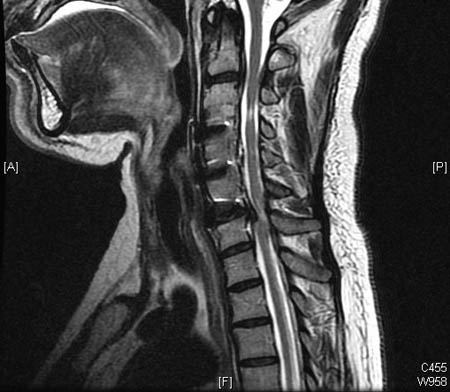

Doença degenerativa da coluna cervical

Compressão da medula espinhal prévia em C3/4 na ressonância nuclear magnética (RNM) sagital de T2, com alterações residuais em T2 e nova compressão em C2/3 e C6/7, com alterações em T2

Dennis A. Turner, MA, MD